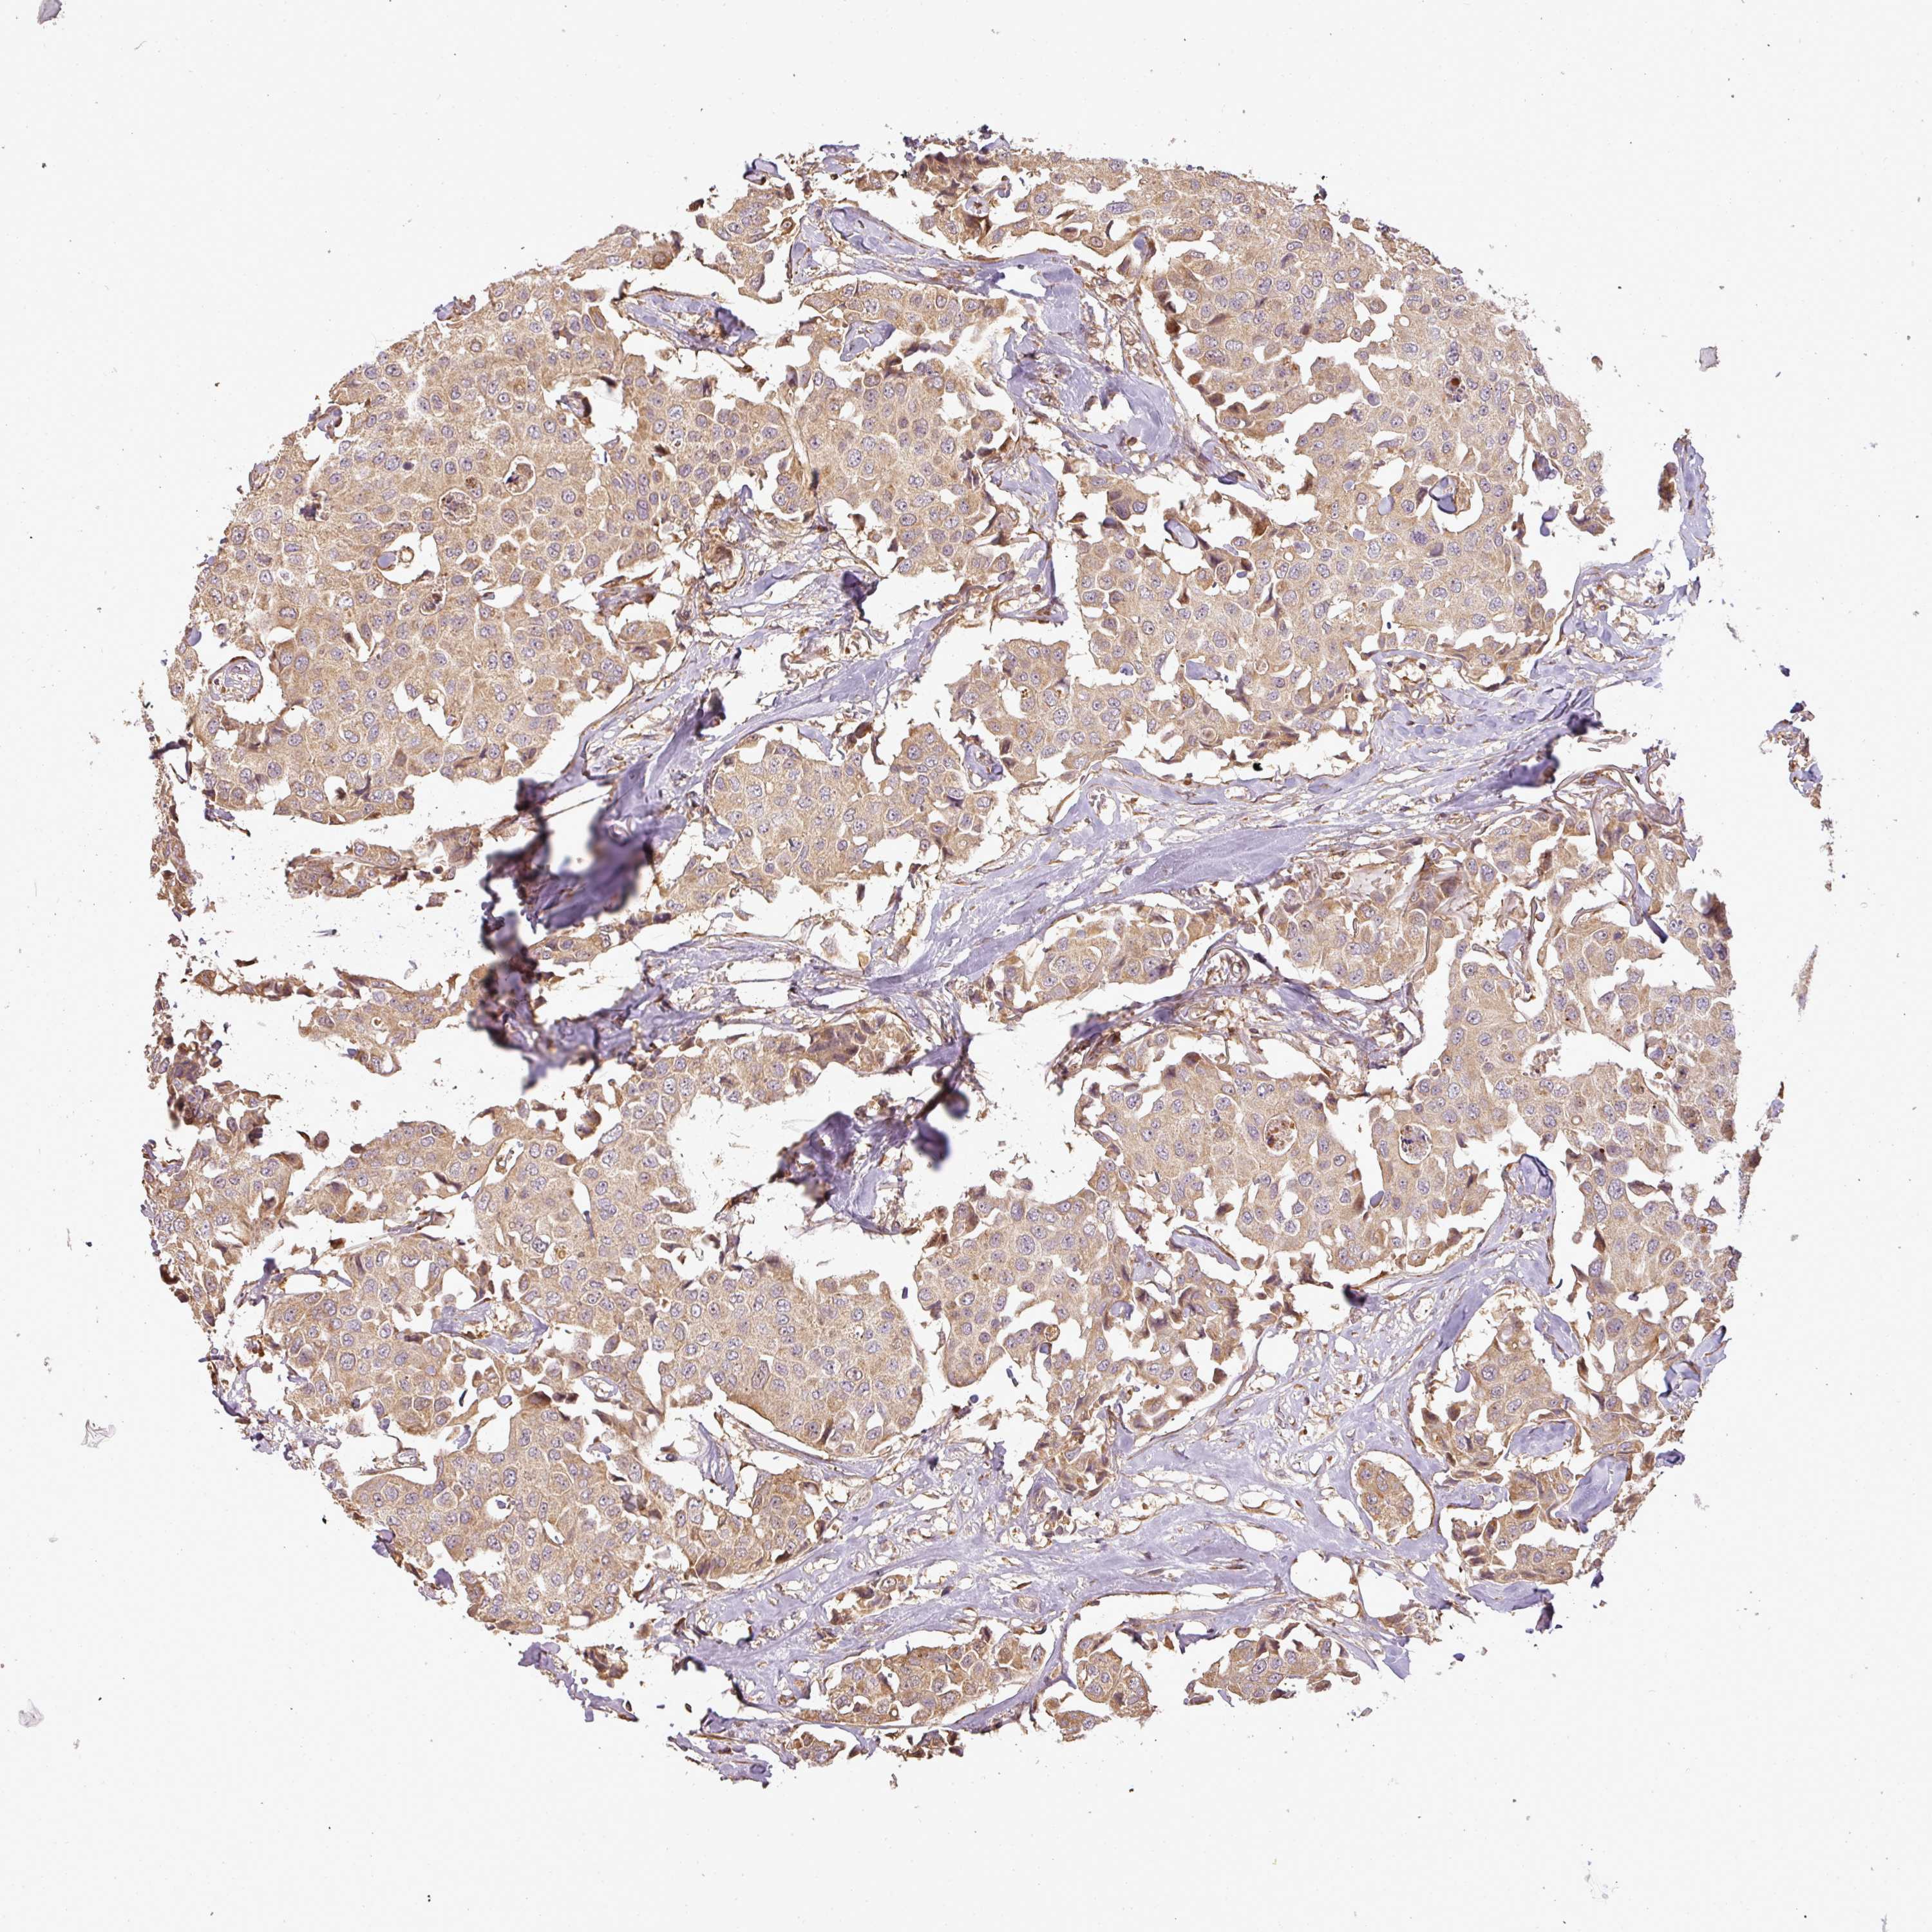

CANCER BREAST CANCER Show tissue menu

BRCA TCGA BRCA VALIDATION PROTEIN EXPRESSION